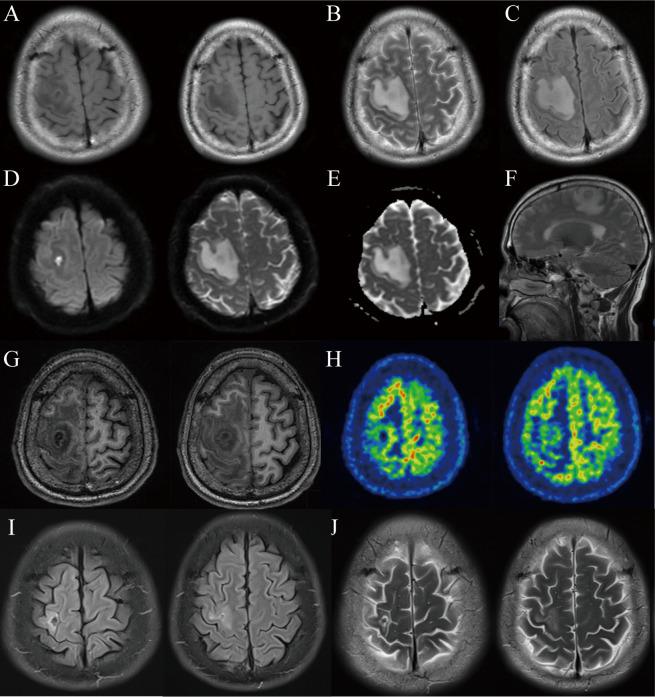

Brain abscess is life-threatening and carries a high risk of mortality. Despite advances in sensitive imaging techniques, effective antimicrobial therapies, and sophisticated surgical procedures, diagnosing and treating brain abscesses remains challenging. Although empirical antimicrobial therapy and neurosurgery are considered primary treatments for brain abscesses, their efficacy is limited by potential side effects including neutropenia development, the need for repeat surgeries, and the risk of new-onset epilepsy. Here, we present a case of a 52-year-old male patient who experienced paroxysmal convulsions accompanied by left-sided limb weakness and numbness for over 2 months. Despite a brain MRI revealing a multilocular cystic lesion in the right frontal lobe, with about 28 mm × 19 mm × 21 mm in size, the patient declined neurosurgical interventions. After completing a 6-week course of antimicrobial therapy, the patient sought traditional Chinese medicine (TCM) treatment. As a result, the patient remained free of paroxysmal convulsions for about 60 days after a 4-month TCM treatment. A follow-up MRI imaging at 8 months showed a reduction in the size of the lesion in the right frontal lobe to 8 mm × 4 mm. To the best of our knowledge, this is the first well-documented case of a brain abscess that was successfully managed with a combination of antimicrobial therapy and TCM. This case report suggests that TCM may provide significant supplementary benefits in managing infections like brain abscesses. However, further evidence from prospective studies is necessary to substantiate the efficacy of Chinese herbal medicine for the treatment of brain abscesses.

脑脓肿具有生命威胁性,死亡率较高。尽管敏感的影像学技术、有效的抗菌治疗和复杂的手术程序都有所进步,但脑脓肿的诊断和治疗仍然具有挑战性。尽管经验性抗菌治疗和神经外科手术被认为是脑脓肿的主要治疗方法,但它们的疗效受到潜在副作用的限制,包括中性粒细胞减少症的发展、需要重复手术以及新发性癫痫的风险。在这里,我们报告了一名 52 岁男性患者的病例,该患者经历了阵发性抽搐,伴有左侧肢体无力和麻木超过 2 个月。尽管脑部 MRI 显示右额叶有一个多房囊性病变,大小约为 28mm×19mm×21mm,但患者拒绝接受神经外科手术干预。在完成 6 周的抗菌治疗后,患者寻求了中医(TCM)治疗。结果,患者在接受了 4 个月的 TCM 治疗后,大约 60 天没有阵发性抽搐。8 个月时的随访 MRI 成像显示右额叶病变的大小缩小到 8mm×4mm。据我们所知,这是首例经充分记录的脑脓肿病例,成功地通过抗菌治疗和 TCM 联合治疗得到了控制。该病例报告表明,TCM 可能在管理脑脓肿等感染方面提供显著的补充益处。然而,需要前瞻性研究的进一步证据来证实中药治疗脑脓肿的疗效。